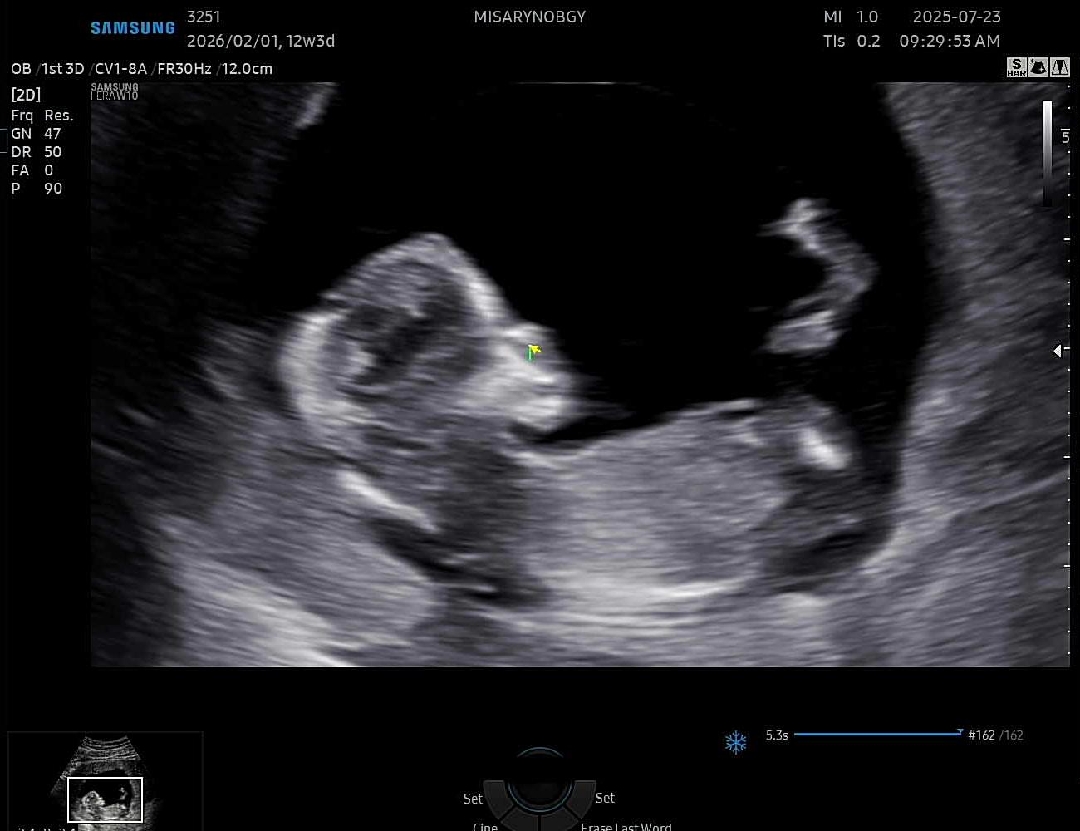

각도법 궁금합니당ㅜㅜ

성별추측 부탁드립니다ㅜㅜ